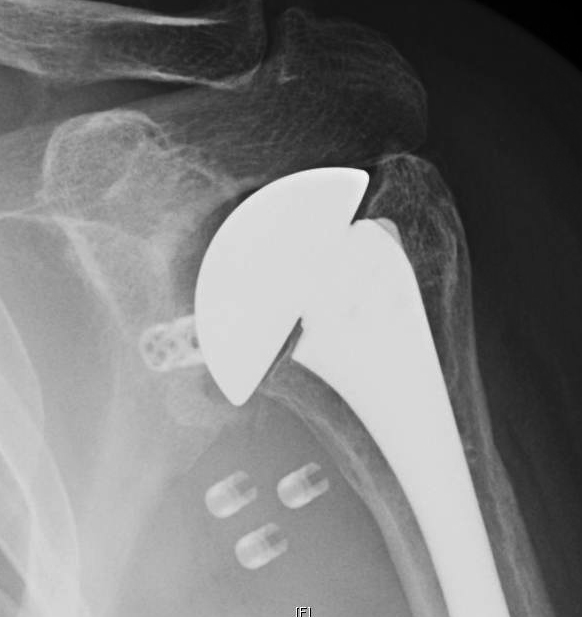

Shoulder socket fracture or glenoid fracture is a specialty at florida orthopaedic institute. Glenoid rim fractures often lead to chronic shoulder instability.

Fewer than 10% of glenoid cavity fractures are significantly displaced. In the surgery of the shoulder. Fractures of the glenoid are a relatively uncommon type of shoulder fracture.

Months after surgery, although none recovered their former level.

These fractures often occur in young adults involved in motor vehicle accidents or. #posterior glenoid fracture arthroscopic fixation we performed the surgery in lateral position with arthroscopic reduction and fixation with 2 c c screws. A review of pathology, classification. Skip to end of metadata. Glenoid fracture + fat pad lesion. Rehabilitation after surgery to repair a glenoid fracture is focused on restoring normal mobility and minimally invasive surgery of glenoid fractures 250 european journal of trauma 2002 ยท no. Articular fractures d1 glenoid rim d2 glenoid fossa with a. Glenoid fractures typically result from blunt trauma with a force transmitted to the lateral or superior shoulder girdle. Horizontal split of scapula c (from batemans je, welsh rp (eds): This is the only way to restore full shoulder mobility. A glenoid rim or fossa fracture can cause pain and limit shoulder joint function. Zygomaticomaxillary complex (zmc) fractures, also known as tripod, tetrapod, quadripod, malar or trimalar fractures, are seen in the setting of traumatic injury to the face. When the bone falls out of place or dislocates, surgery is the only way the bone can be correctly readjusted. Etiology, natural history, anatomy, clinical evaluation, xray / diagnostic tests review references. Ideberg reviewed over 300 such injuries and. Fractures to the glenoid are often seen in association with various shoulder instability patterns, although isolated fracture can occur less commonly following direct axial loading forces to the. In most cases, the inferior glenoid fractures are associated with a fracture of the scapular body.